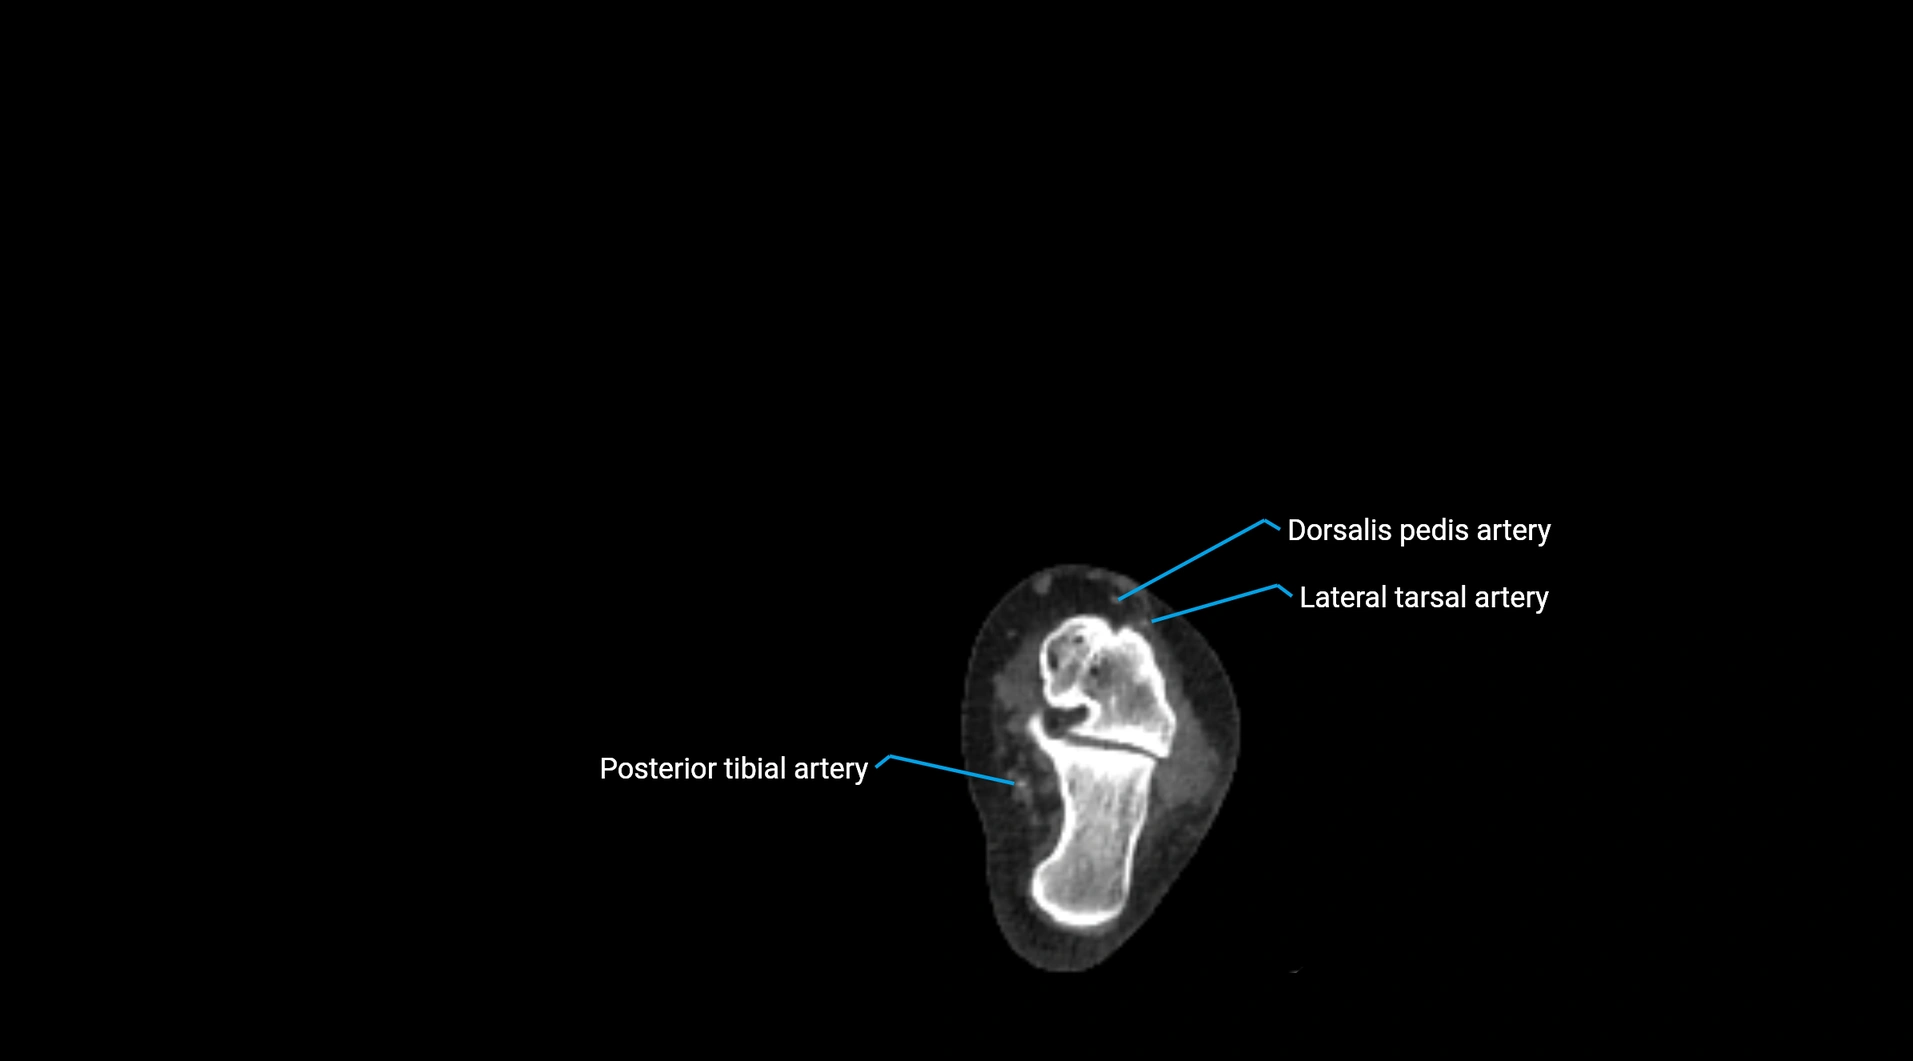

CT Appearance

Non-contrast CT:

• Appears as a tubular soft tissue structure anterior to vertebral bodies

• Calcified atherosclerotic plaques appear as hyperdense foci along the wall

• Useful for screening abdominal aortic aneurysm (AAA) size and mural calcification

Contrast-enhanced CT (CTA):

• Gold standard for abdominal aortic imaging

• Provides excellent detail of lumen, wall, aneurysm, thrombus, and branch vessels

• Multiplanar and 3D reconstructions help in aneurysm measurement, stent graft planning, and dissection evaluation

• Detects acute rupture, traumatic injury, or occlusion with high sensitivity